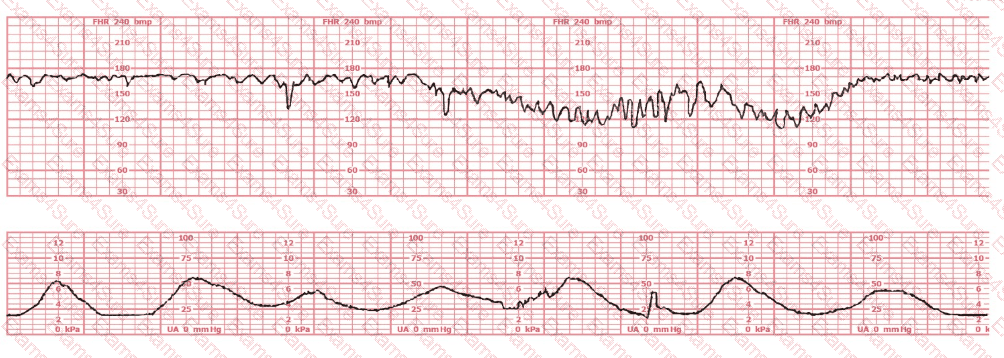

A woman is admitted at 41-weeks gestation for fetal evaluation following a motor vehicle accident. She reports that she hit her abdomen on the steering wheel. The underlying physiology of the tracing is most likely: